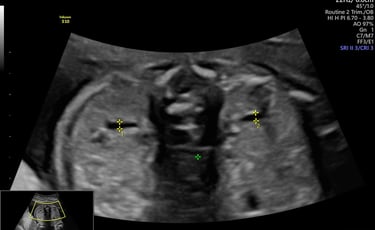

ecografía de crecimiento Doppler

24 - 40 semanas